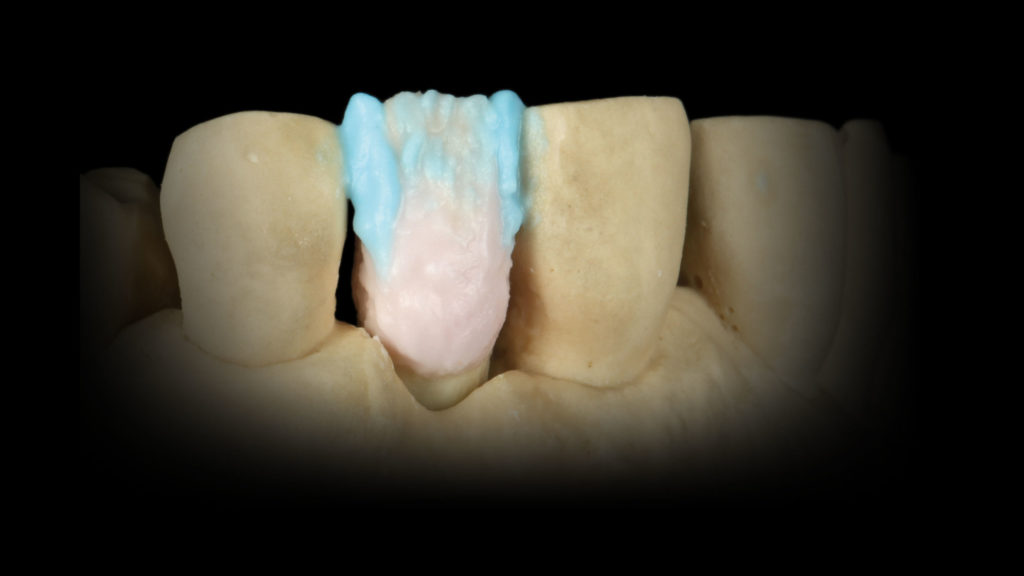

Mit einer dünnen Schicht der 1:1:1-Mischung aus den Mamelon-Massen Gelb-Orange und Rot-Orange sowie der Modifier-Masse Pink Dentin wurde eine höhere Farbsättigung erreicht (Abb. 16). Um die Transluzenz zu den Flanken hin zu verstärken, wurden die Schmelzmassen Natural Enamel Light und Clear im Verhältnis 1:1 angemischt und mesial und distal aufgetragen (Abb. 17). Der Raum zwischen diesen Schmelzleisten wurde labial, aber auch palatinal mit einer 1:1:1-Mischung aus Light, Super Clear Glaze und Violet Glaze gefüllt (Abb. 18 und 19). Ein Streifen des Dentin Modifiers Violett sorgt im mittleren Drittel für einen Lichtabsorptionseffekt (Abb. 20a und b). Nach dem ersten Brand kann man gut erkennen, ob uns der Grundkörper gelungen ist (Abb. 21) oder ob wir den inneren Aufbau intensivieren, reduzieren oder andere Änderungen vornehmen müssen.

Vor dem internen Bemalen (Internal Live-Staining) wurde die Krone etwas in Form geschliffen und dann mit Glasurflüssigkeit befeuchtet. An dieser Stelle zogen wir nochmals die DSLR-Aufnahmen der Ausgangssituation und Nachbarzähne zurate, um relevante Charakteristika erkennen und entsprechend reproduzieren zu können (Abb. 22a bis c). Wir starteten das Internal Staining mit dem Anlegen von Sprüngen, die ausgehend von der Inzisalkante mit Weiß und Creme in Richtung Zentrum der Krone angelegt wurden (Abb. 23 bis 26). Vor dem Fixierbrand wurden die Malfarben noch schnell außerhalb des Ofenraums getrocknet. So wird sichergestellt, dass die Malfarben beim Brennen nicht verlaufen und sich die Position der aufgebrachten Effekte nicht verschiebt (Abb. 27). Da der zu rekonstruierende Zahn für diesen Fall unterschiedliche innere und äußere Merkmale aufwies und dennoch eine in sich geschlossene Einheit ergeben sollte, stellte sich die Schichtung als Herausforderung dar. Die Lösung bildete eine Kombination aus der Internal-Live-Staining-Technik von Meister Hitoshi Aoshima mit Universal Stain and Glaze (Dentsply Sirona) und einer dezidierten Schichtung – und zwar im tatsächlichen Wortsinn in unterschiedlichen Schichten. Denn damit die Technik des Internal Stainings richtig zur Geltung kommt, ist es wichtig, eine korrekte, farbgebende Basis aus Dentin und Schmelz zu schaffen. So, wie wir es in Form des Grundkörpers getan hatten.

Auf den mittels Internal Staining charakterisierten Grundkörper wurde nun mit Dentin Opaque B4 der freiliegende Wurzelbereich akzentuiert. Im zervikalen und mittleren Drittel wurde eine 1:1-Mischung aus Dentin A3,5 und Enamel Clear aufgetragen und ebenfalls mit einer 1:1-Mischung Enamel Light und Enamel Clear das inzisale Drittel vervollständigt. Enamel Extra Light, das an den Rändern aufgetragen wurde, schloss die Schichtung ab (Abb. 28a und b). In den Abbildungen 28c ist der gebrannte Grundkörper der Implantatkrone zu sehen. Dieser Zwischenschritt war somit abgeschlossen. Würden wir Begriffe aus dem Wortschatz eines Visagisten verwenden, dann könnte man diesen Schritt als Foundation-Auftrag bezeichnen. Auf diese Grundierung, die aber auch schon Farbinformationen und Charakteristika aus der Tiefe beinhaltet, wird nun das Make-up aufgetragen.